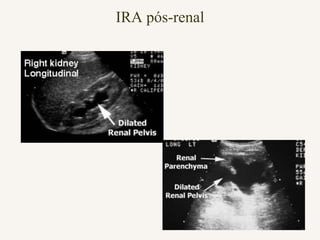

b)Pós – Renais: Obstrução do Fluxo

Urinário

 obstrução ureteral (cálculos, coágulos).

 obstrução colo vesical (hiperplasia

próstata).

 obstrução uretral (cálculos).

IRA pós-renal